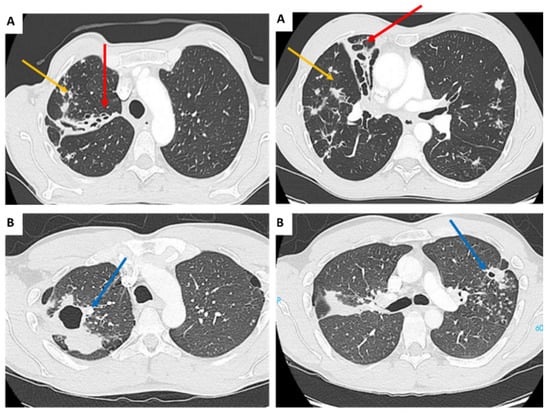

2.3. Diagnosis Criteria